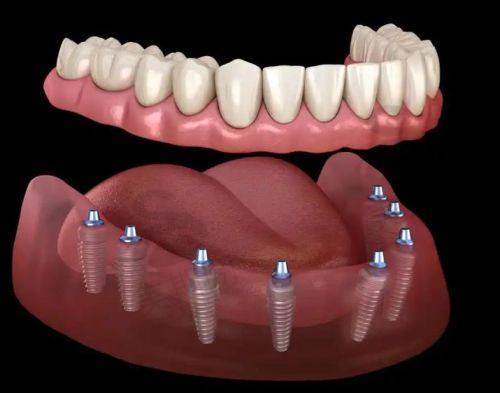

诊疗范围涵盖种植牙、牙齿矫正、综合口腔(补牙、拔牙、洗牙等)、儿童口腔等全品类项目,其中种植牙与牙齿矫正为特色王牌项目:种植牙领域可开展微创种植(切口≤3mm)、即刻种植(当天种牙当天戴牙)及半/全口All - on - 4/6疑难种植技术,累计完成种植实例超4000例;牙齿矫正方面,隐形矫正(时代天使、隐适美)实例突破500例,青少年早期干预与成人复杂错颌畸形矫正技术与一线城市同步。

种植牙技术:采用3D数字化种植系统,术前通过CBCT扫描获取牙槽骨三维数据,结合3D导板精细定位种植体角度与深度,实现“毫米级误差”植入,降低手术风险。针对半/全口缺牙患者,医院开展All - on - 4/6即刻负重技术,仅需4 - 6颗植体即可支撑半口/全口牙齿,手术当天即可戴临时牙冠修复咀嚼,相比传统种植减少30%费用与6个月等待时间。此外,微创种植技术(切口≤3mm)无需缝合,术后24小时即可正常进食,适合怕痛、修复需求高的患者。

4. 秦皇岛蓝天口腔医院半口All - on - 4种植:2.8万元起(4颗植体+临时牙冠);

5. 秦皇岛蓝天口腔医院全口All - on - 6种植:5万元起(6颗植体+终身维护);

“我今年65岁,下半口牙掉了8颗,吃饭只能吃软的。在蓝天口腔找温长兴院长做了All - on - 4半口种植,手术当天就戴上了临时牙,回家就能吃面条!现在3个月了,啃苹果、吃肉都没问题,花了4万多,比去北京便宜一半。医院服务也好,术后每周都有护士打电话问修复情况,值!”——王阿姨(退休教师,半口种植患者)